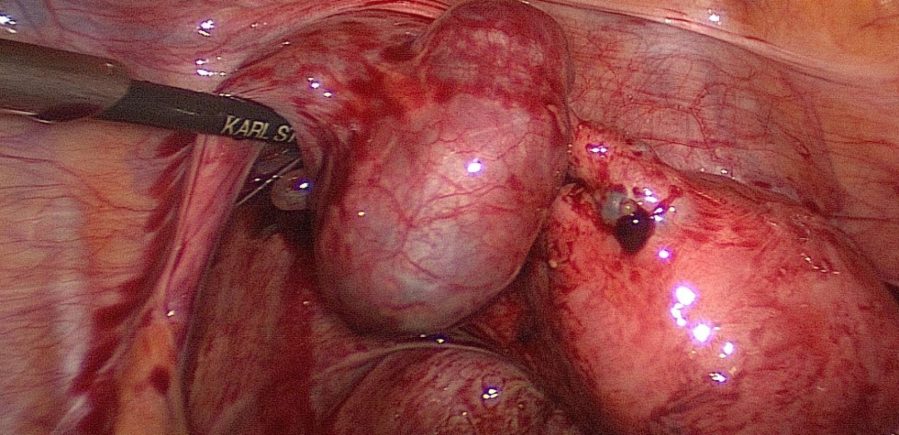

Inspect the organs in the small pelvis thoroughly and drain any blood that may have accumulated.

Know your situs: in this case there are pelvic adhesions after pelvic inflammatory disease.

Visualize the ectopic pregnancy.